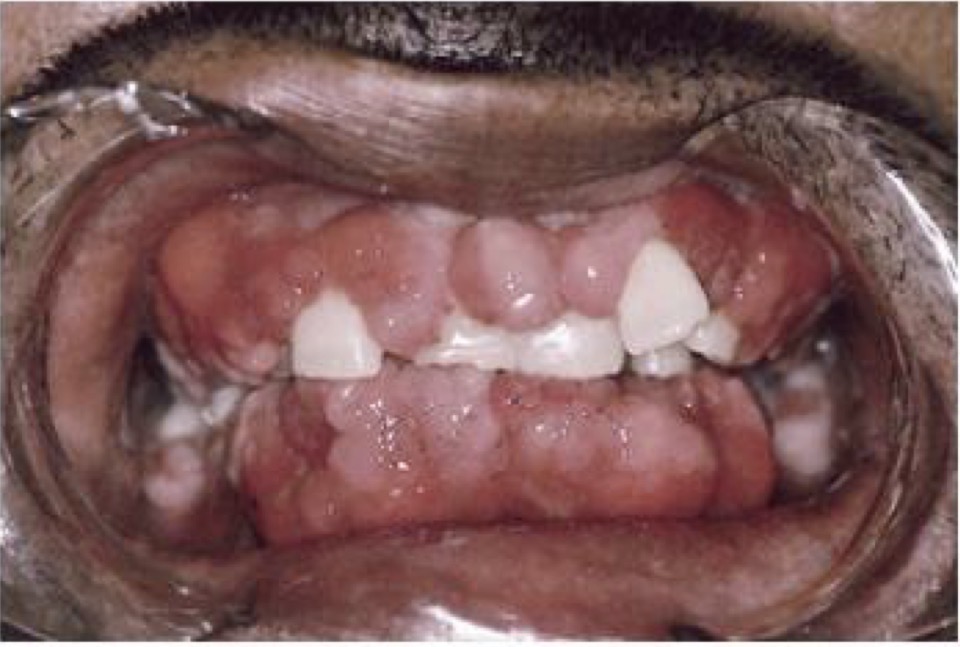

BN CÓ GAI NƯỚU TĂNG SINH, SƯNG TO, CẮNG BÓNG

SỜ DAI, KHÔNG ĐAU, KHÔNG CHẢY MÁU *

CHẨN ĐOÁN

TRIỂN DƯỠNG NƯỚU DO THUỐC PHENYTOIN

TRIỂN DƯỠNG NƯỚU DO DÙNG THUỐC PHENYTOIN

CHẨN ĐOÁN?